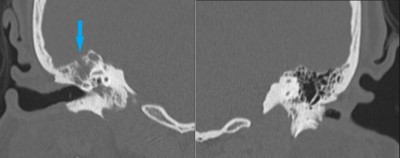

Intraoperative photo demonstrating the operative approach. A right temporal craniotomy has been made and the covering of the brain, the dura mater, is being dissected off of the base of the skull. Orientation: this is the right side of the head; the ear is just off the top of the frame (green star(*)), the nose is to the left, the back of the head the right, and the top of the head is toward the bottom.

Intraoperative video demonstrating the dissection of the encephalocele. Note the band of tissue extending from the skull base defect on the top of the image through the dural defect toward the bottom. This is the encephalocele.